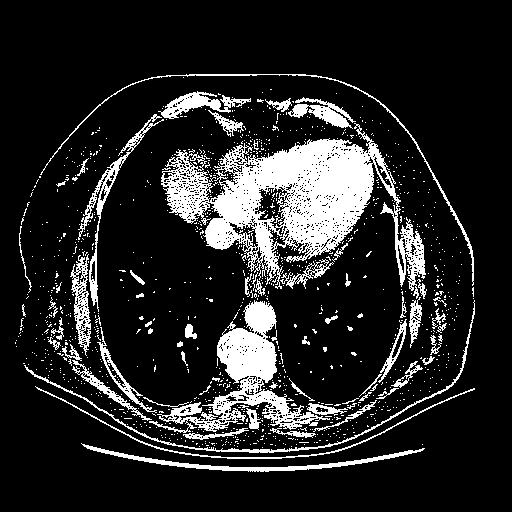

Original NATIVE CT scan (input)

Full window (WL 1023.5, WW 4095 β†’ Low βˆ’1024, High +3071)

Actual HU range: [-1024.0, 3071.0]

Lung window (WL -600, WW 1500 β†’ Low βˆ’1350, High +150)

Actual HU range: [-1350.0, 150.0]

Mediastinum window (WL 40, WW 400 β†’ Low βˆ’160, High +240)

Actual HU range: [-160.0, 240.0]